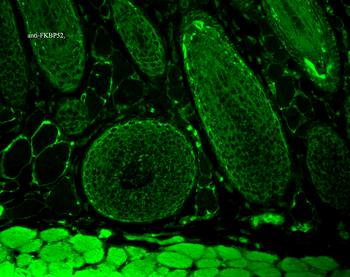

50 μl, 100 μl, 200 μlFKBP52 Antibody: APC [orb147210]

ICC, IF, IHC

Canine, Hamster, Human, Mouse, Rat

Mouse

Monoclonal

APC

100 μgFKBP52 Antibody: Biotin [orb147211]